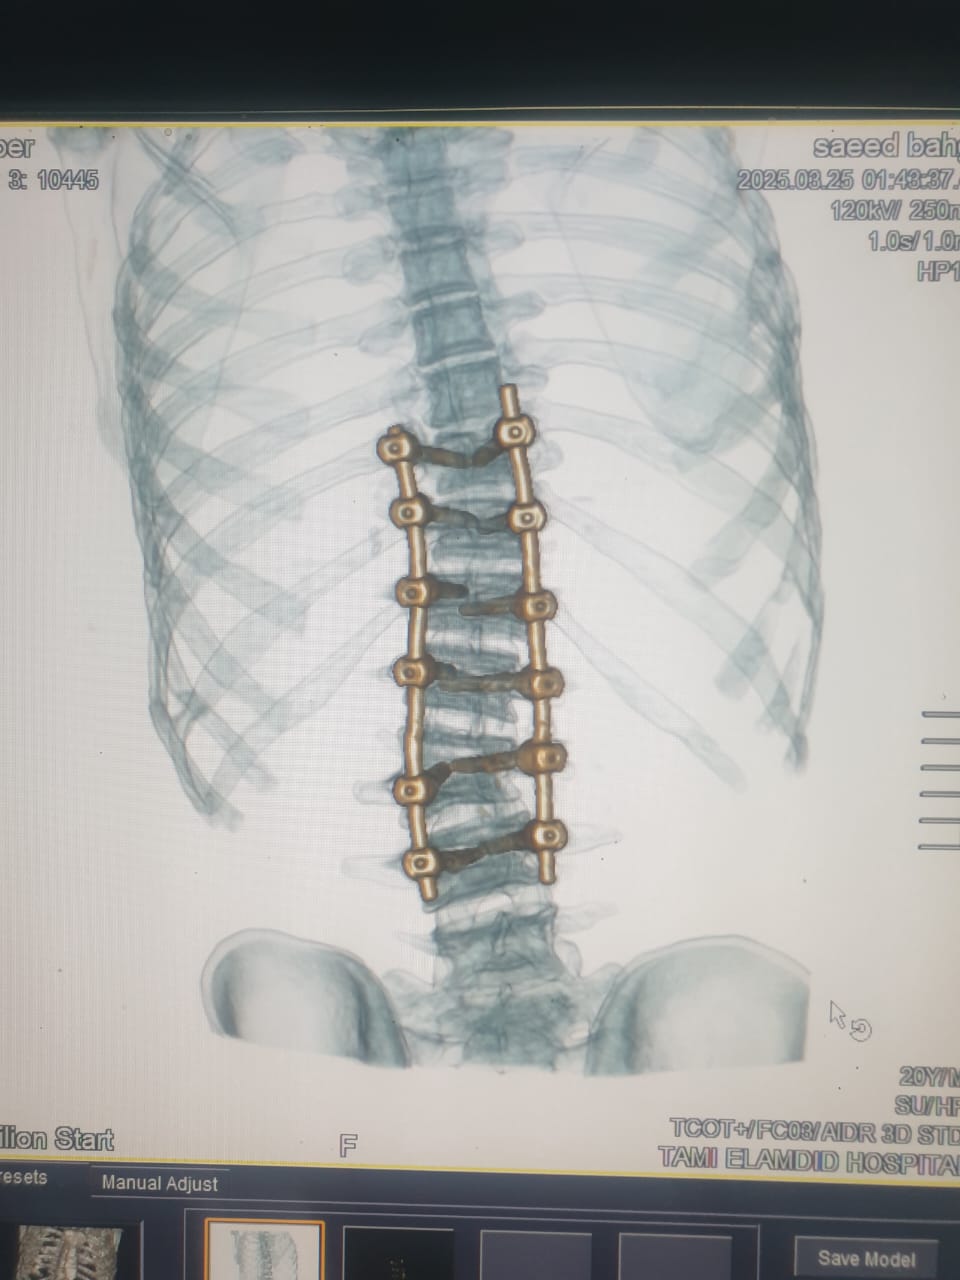

نجح فريق طبى بقسم جراحة المخ والأعصاب بمستشفى تمى الأمديد بالدقهلية فى إجراء اول جراحة دقيقة لإصلاح اعوجاج بالعمود الفقرى لشاب يبلغ من العمر 21 عاماً .

وأضاف مدكور أنه جرى استقبال المريض وهو يعانى من الالام شديدة بالظهر مع عدم الاستجابه للعلاج الدوائي والعلاج الطبيعى وعقب الفحص تبين وجود اعوجاج بالفقرات الصدريه والقطنيه بالعمود الفقري.

فيما أوضح الدكتور احمد البيلى وكيل المديرية للطب العلاجى أنه عقب مناظرة الاشعة والفحوصات تم إجراء العملية التى استغرقت 4 ساعات كاملة لإصلاح الاعوجاج بواسطه تثبيت الفقرات الصدريه والقطنيه واستعدال العمود الفقرى مع خروج المريض من المستشفى وتحسن حالته